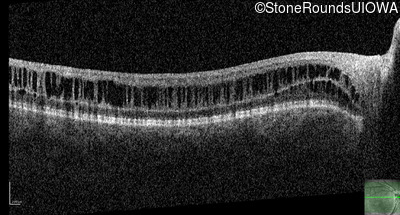

XL Retinoschisis (IIIB1)

Age at visit: 6 years

OD OS

This 6 year old boy began sitting very close to the television at age 2.

Diagnosis & molecular findings

XL Retinoschisis RS1 Tyr93Stop TAT>TAG   XL